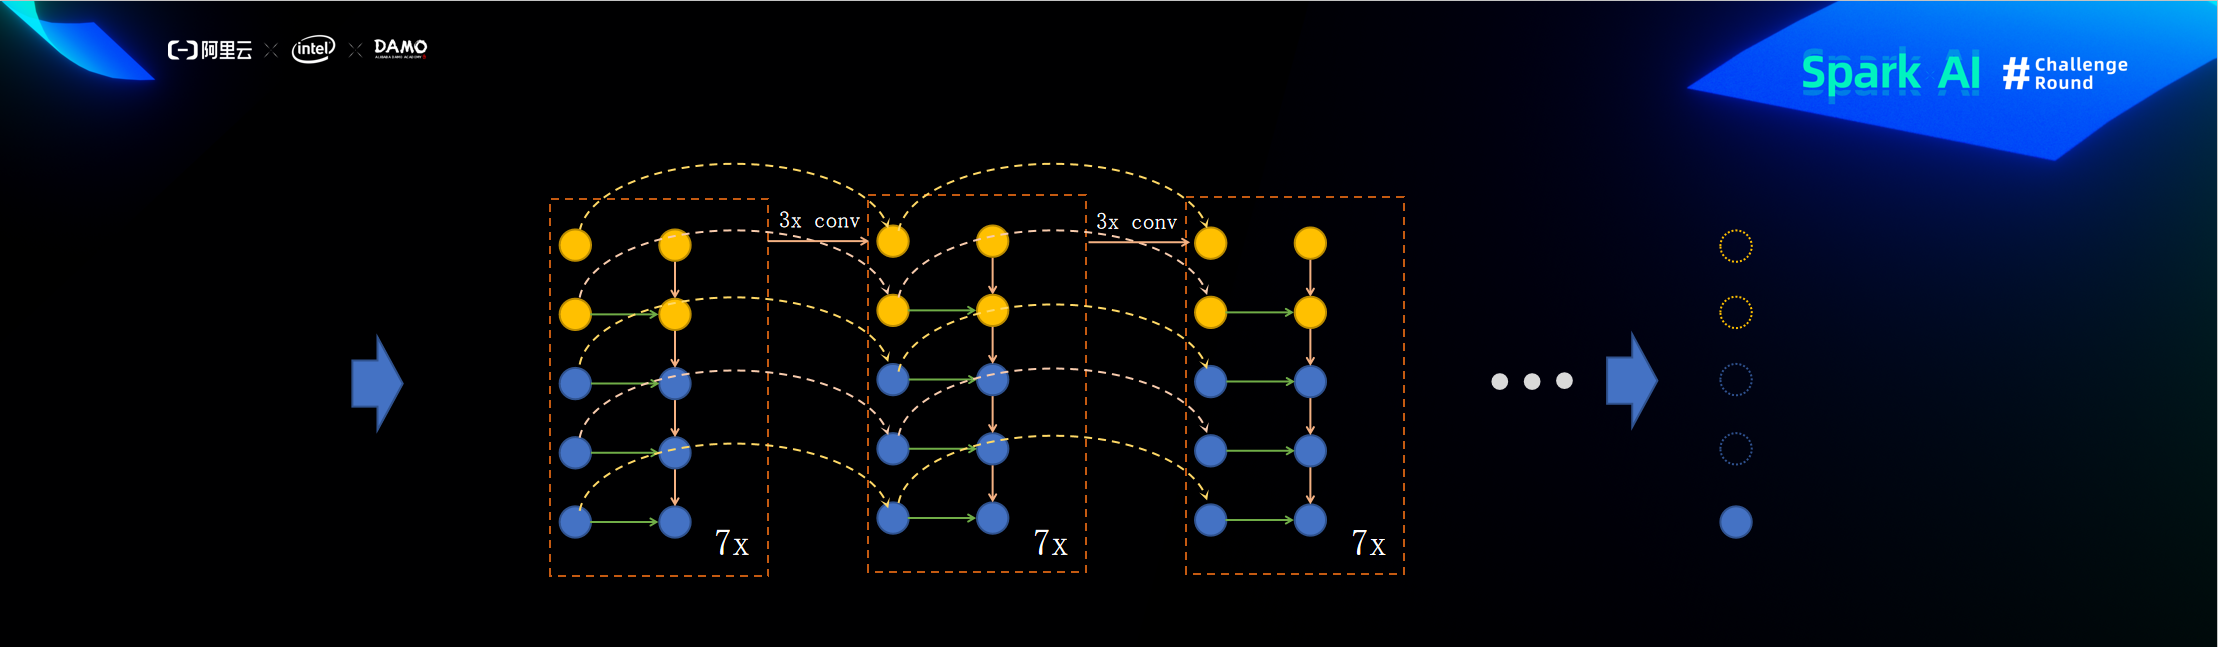

ResFPN结构

以上便是我此次参加比赛所使用的模型,提交分数为0.633,但此模型其实还可以做些改进,比如将backbone出来的feats继续下采样的resnet换成efficientnet block,ResFPN也可以继续改进到ResFPN2.0,ResFPN里的每层fpn_layer其实就是一次自顶向下融合,ResFPN2.0与第一代ResFPN的区别就是ResFPN2.0每一次自顶向下融合之后最顶上的特征图就进行一次卷积之后再进行下一次融合。